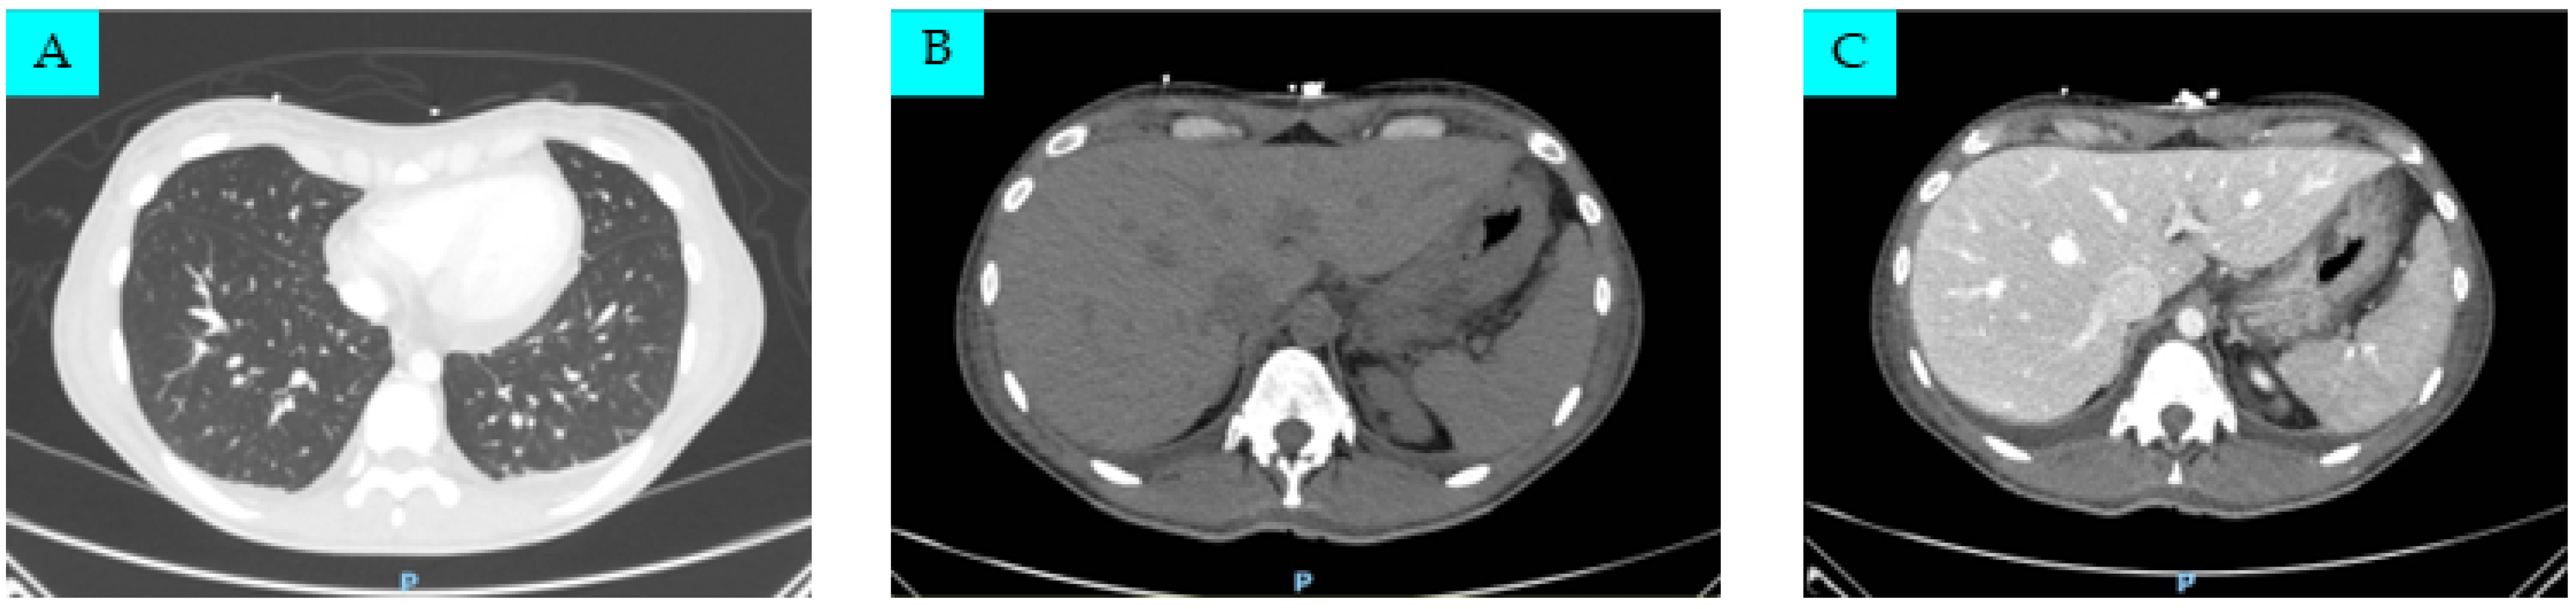

2. Case Presentation